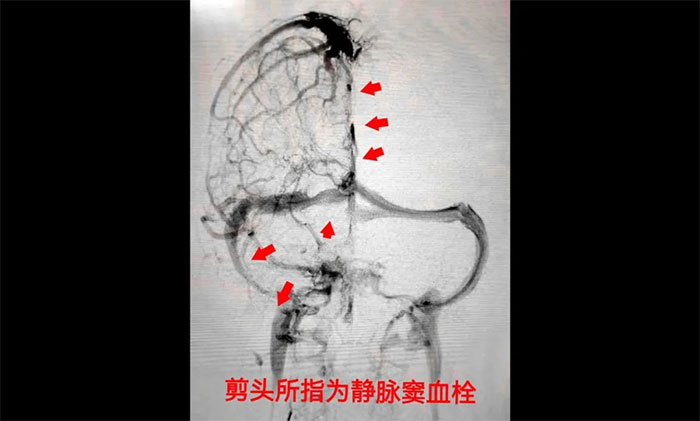

術(shù)中,席剛明教授在4A病區(qū)副主任王貴平博士協(xié)助下,憑借二十多的介入手術(shù)經(jīng)驗(yàn)小心探索,一邊“疏通”,一邊不斷切換正位及側(cè)位造影,避免造成其他損傷。經(jīng)過(guò)3個(gè)多小時(shí)的奮戰(zhàn),經(jīng)多次支架取栓、導(dǎo)管抽吸,取出大量暗紅色血栓,復(fù)查造影見(jiàn)上矢狀竇、竇匯、右側(cè)橫竇、乙狀竇顯影改善,患者靜脈竇順利再通。術(shù)后,患者癥狀好轉(zhuǎn),癲癇未再發(fā)作,頭痛惡心等癥狀消失,最終脫離了生命危險(xiǎn),逐步恢復(fù)健康。

▲ 顱內(nèi)靜脈竇血栓形成